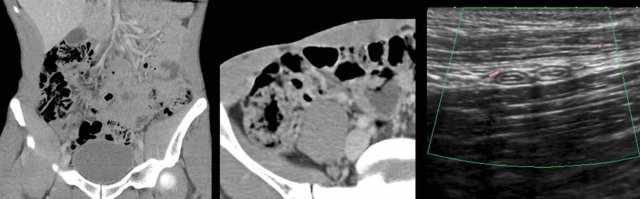

A 9-year-old, with persistent RLQ pain and painful micturition, two weeks after appendectomy for perforated appendicitis.

CRP 220.

He was not very ill.

US shows a large, irregularly defined Douglas abscess with reactive thickening of the bladder wall (**).

He had a few days of smelly stool (spontaneous evacuation of pus to the rectum) and made a full recovery without antibiotics or surgery.